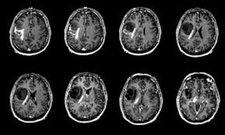

Tanı YöntemleriAkciğer tümörü tanısı, hastanın belirtileri ve fiziksel muayenesi ile başlayarak çeşitli testler ile devam eder. Tanı yöntemleri arasında: